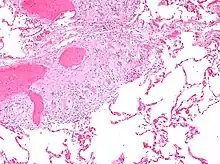

Additional images